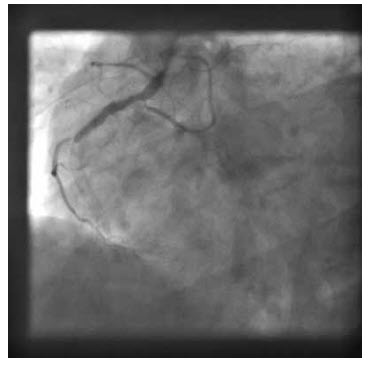

A 45-year-old diabetic man is admitted directly to the catheterization laboratory with chest pain and ST elevation. He had elective angioplasty a week previously for stable angina. He received drug-eluting stents and is taking aspirin and clopidogrel. The relevant angiographic image is shown

What is the diagnosis?

The clinical history suggests acute stent thrombosis. The image shows occlusion of flow at the proximal edge of a stent.